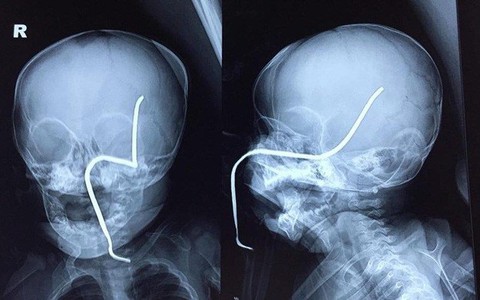

TTO - Một bé gái 8 tháng tuổi ở Sơn Tây, Hà Nội bị máy cắt cỏ vận hành gần đó làm bắn thanh sắt xuyên qua má trái gây thủng sọ.

TT - Theo bác sĩ Hoàng Sơn, bé Lan nhập viện ngày 5-10 do tái hẹp thực quản dù bé được nong, đặt stent ba lần trước đó.